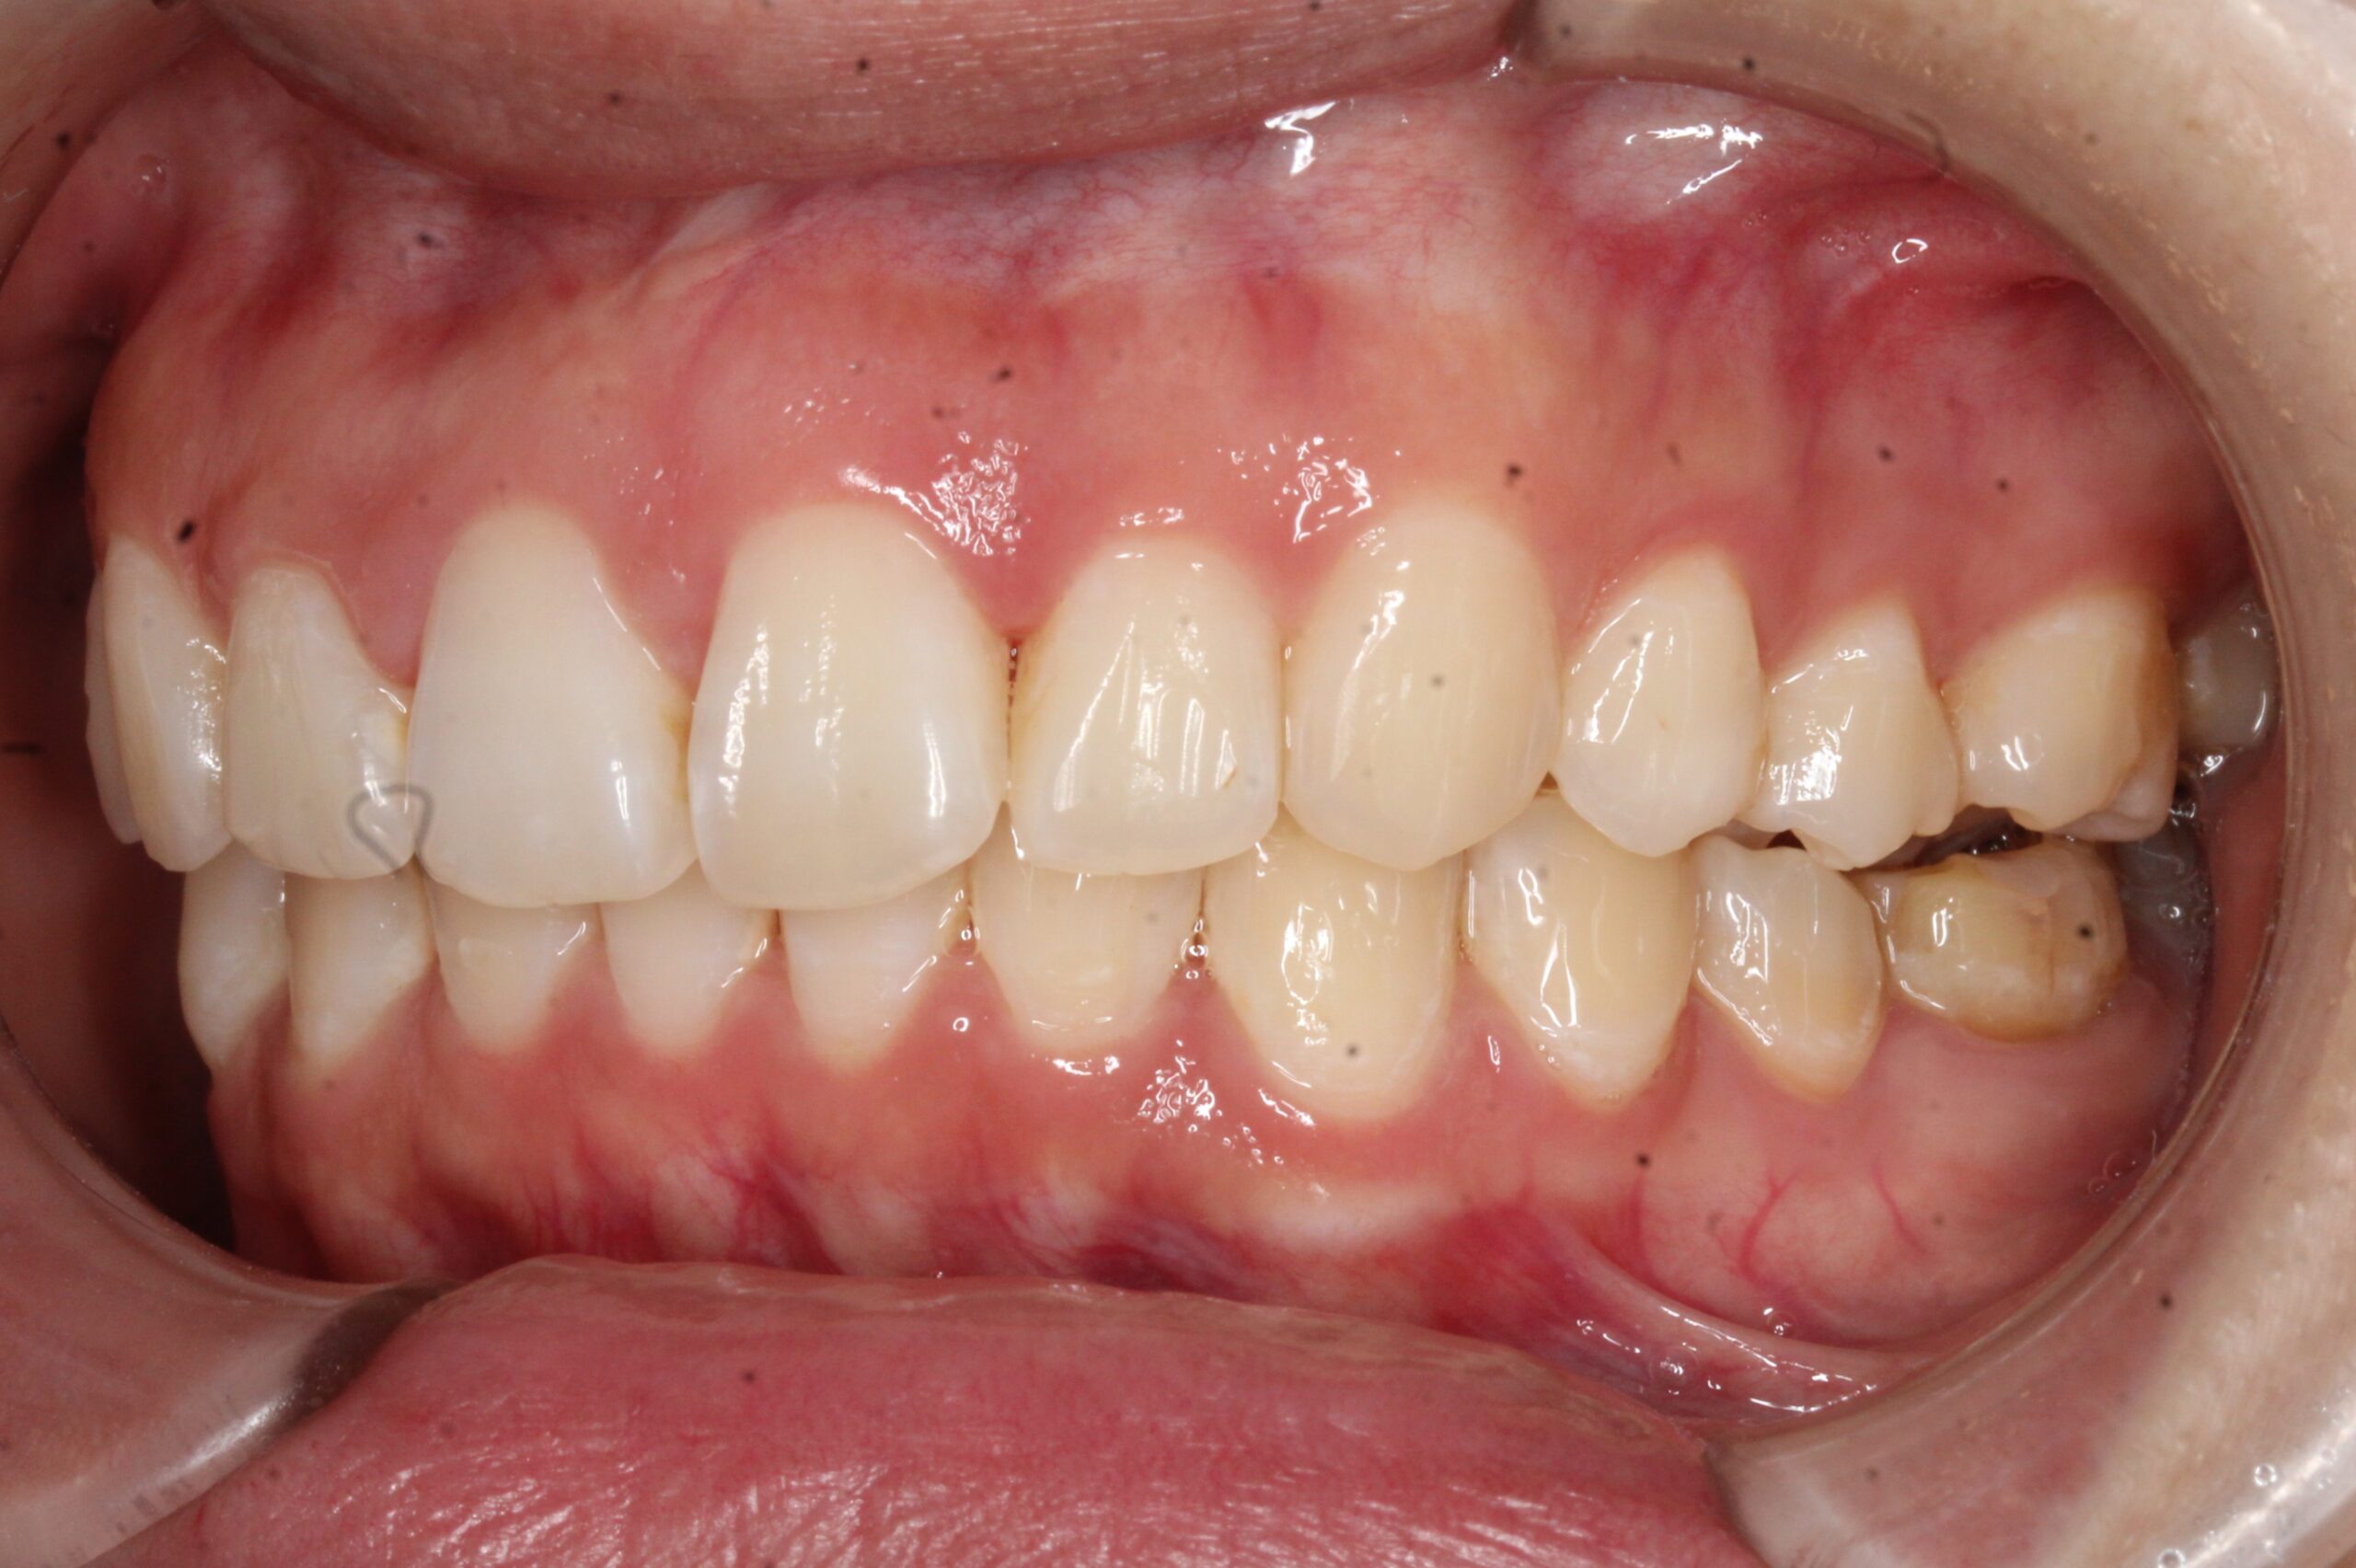

矯正術前:正面

矯正術後:正面